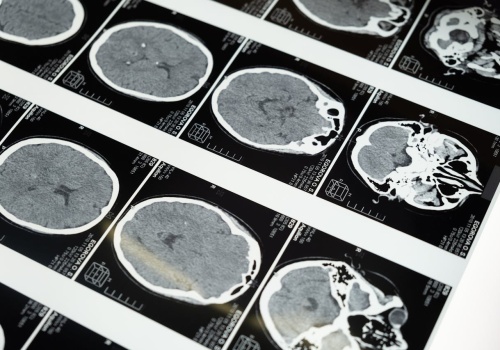

Naukowcy zmodyfikowali IL-10 i poprawili funkcje poznawcze u starych myszy. Czy immunoterapia spowolni starzenie mózgu? Artykuł Czy można odmłodzić mózg? Zmodyfikowana terapia immunologiczna poprawia pamięć u myszy pochodzi z serwisu Alert Medyczny.

Czy trening umysłowy może cofnąć zegar biologiczny naszego mózgu o dekadę? Naukowcy z McGill University w Kanadzie przeprowadzili badania nad aplikacją BrainHQ, opracowaną przez amerykańską firmę biotechnologiczną Posit Science Corporation. Wyniki są...

Po osiągnięciu dorosłości wraz z wiekiem nasz mózg kurczy się o ok. 5-10 proc. — informuje serwis Poradnik Zdrowie. Największe zmiany, prowadzące do rozmaitych problemów i zaburzeń, zaczynają się już u sześćdziesięciolatków. Sprawdź, jak po 60. roku...